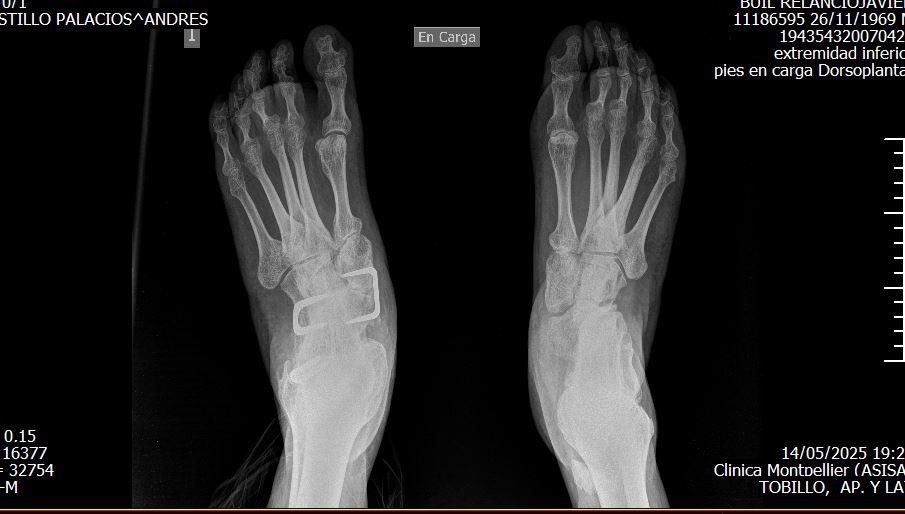

Desde que nací, mi vida ha estado marcada por un reto físico: pies zambos. Esto supuso operaciones, limitaciones de movilidad y dolor constante durante años. Con el tiempo, mi capacidad para caminar se redujo tanto que dependía de un bastón y podía dar solo pasos cortos y limitados.